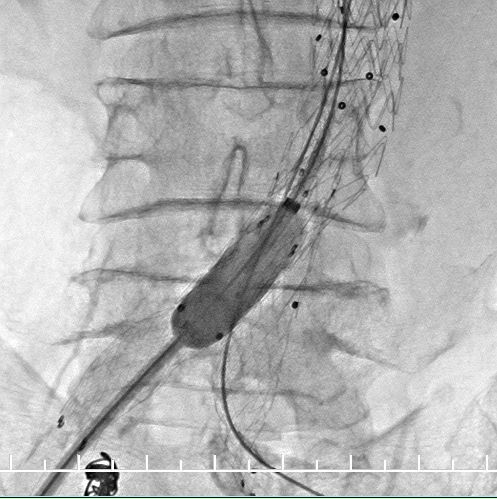

右侧超硬导丝到位,试图纠正瘤颈角度,结果不佳。支架必须使用柔顺性较好的,美敦力(28mm-16mm*160mm,Endurant II)是较好的选择。

支架柔顺性好,这是信心的来源。

右肾动脉闭塞,精确定位左肾动脉开口释放支架。